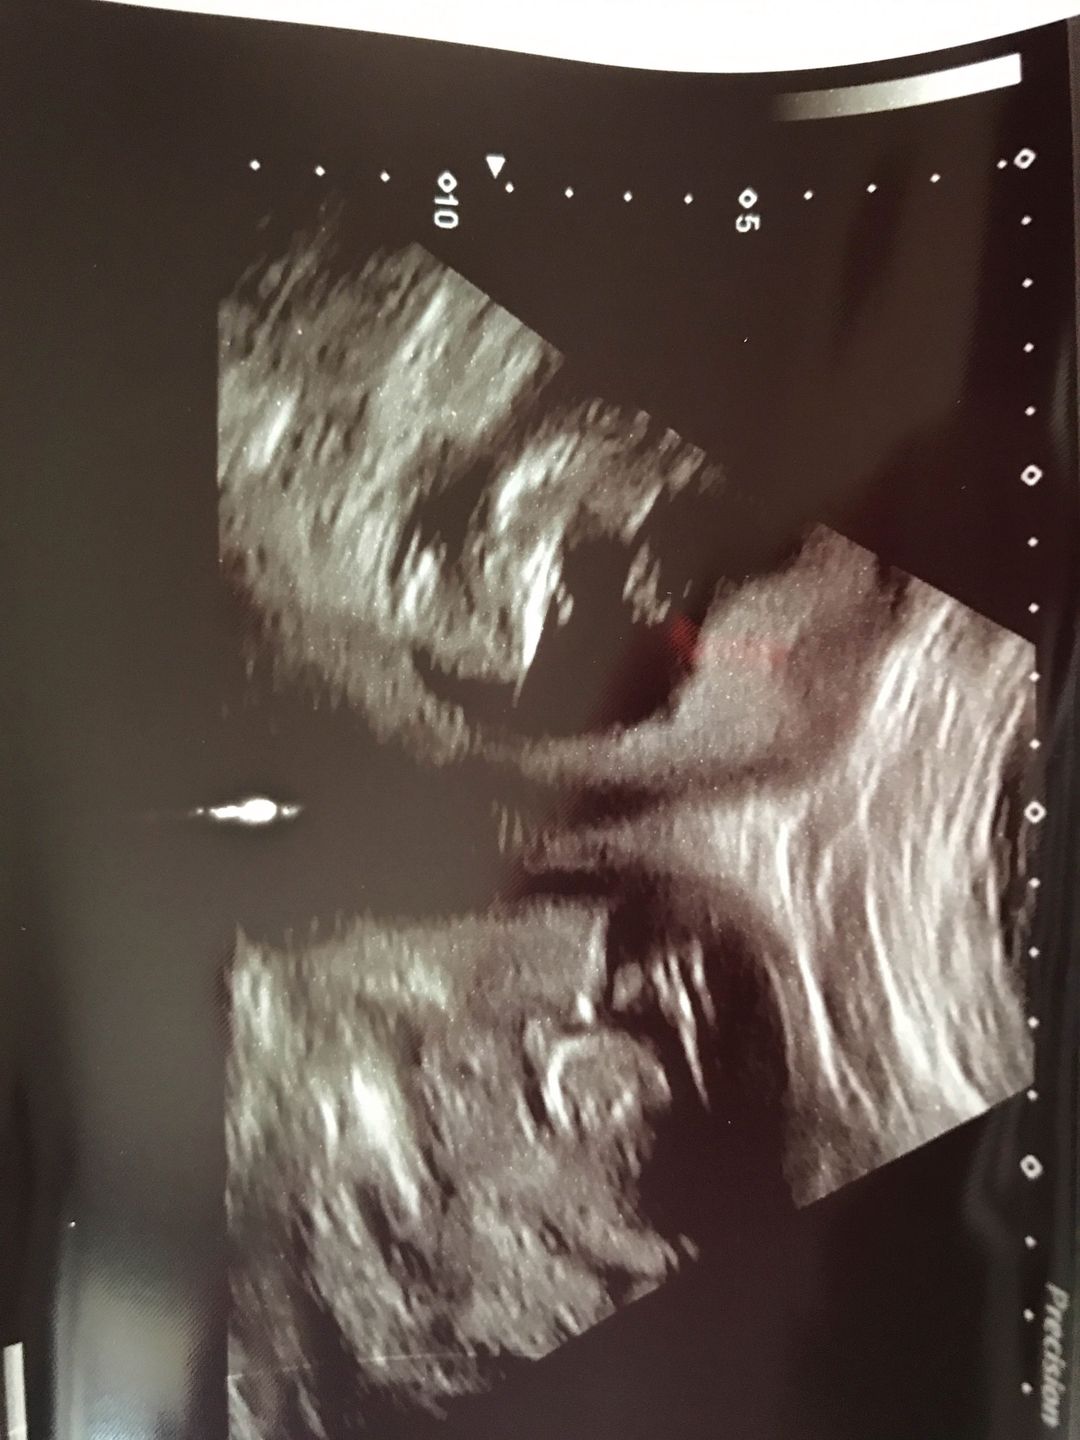

Jennifer Ashwood dowiedziała się, że ma dwie macice, gdy okazało się, że w każdej z nich zagnieździł się zarodek. To niespotykana sytuacja. Lekarze podkreślają, że taka ciąża zdarza się raz na pół miliarda przypadków - informuje "New York Post".

31-latka została objęta specjalną opieką medyczną. Jej przypadłość nie wymagała leczenia, jednak prawdopodobieństwo poronienia było odrobinę większe niż w przypadku zwykłej ciąży. W 28. tygodniu Jennifer zaczęła rodzić, jednak lekarzom udało się powstrzymać skurcze. Młoda matka wspomina, że specjaliści tak naprawdę nie wiedzieli, jak może wyglądać poród. Spekulowano, że każde z bliźniaków urodzi się przez cesarskie cięcie.

Poppy i Piran urodzili się w 34. tygodniu ciąży. Chłopiec przyszedł na świat dzięki cesarskiemu cięciu, dziewczynka - drogą naturalną.